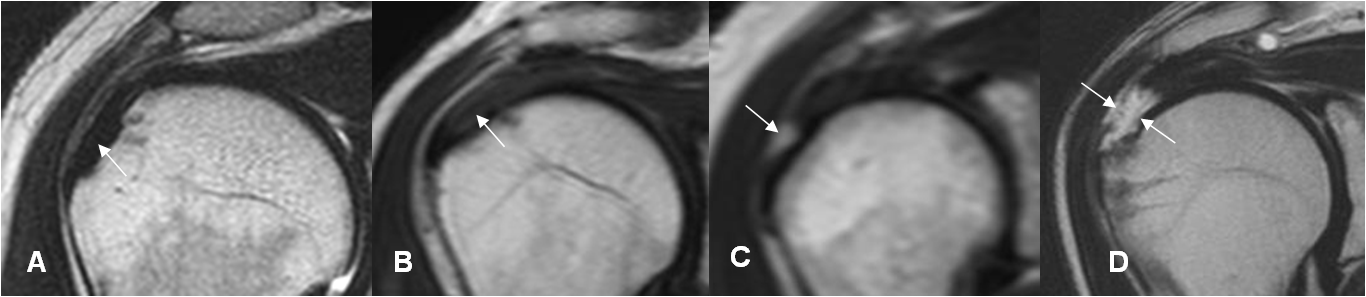

Fig 125. Retracción en las rupturas del supraespinoso.

A, B, C y D: RM coronal en STIR. Diferentes grados de retracción, en rupturas completas del supraespinoso. A: Pequeña, B: Mediana,

C: Larga y D: Masiva.